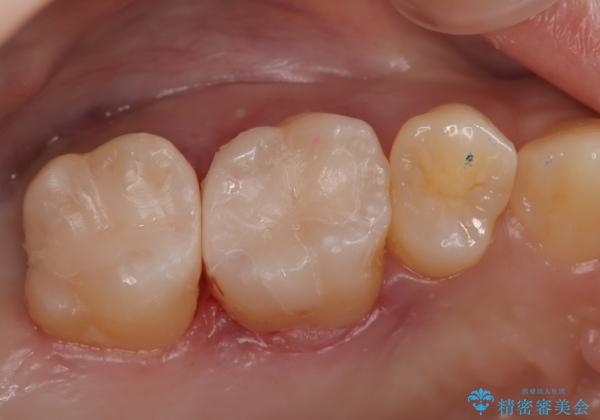

- 金属を外してセラミックを入れたいことを主訴に来院された患者さんです。

セラミックインレーにて修復を行いました。

当院でのセラミックインレーは、ラバーダムを使用して装着しております。